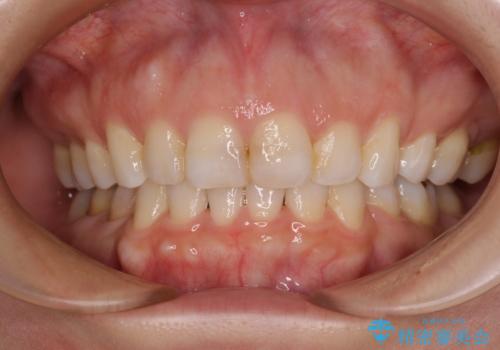

前歯のデコボコをインビザラインでスッキリと仕上げる

- 上下前歯のデコボコと奥歯の銀歯を気にして来院された患者様です。

口元をインビザラインにより歯列を整え、その後に失活している奥歯をオールセラミッククラウンにて補綴治療することとしました。

長時間のマウスピース装着に協力いただき、自然な口元に仕上げることができました。

気になっていた銀歯もオールセラミッククラウンで本物の歯のようになり、患者様には大変満足していただきました。